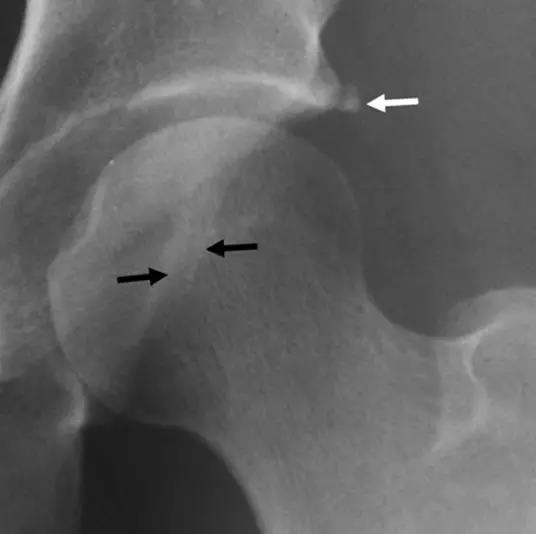

凸轮撞击型FAI▼

- 股骨头颈联合处前上缘骨性突起。

- 非圆形的股骨头。

- 股骨头颈联合处前缘骨性突起、骨质硬化,α角增大。